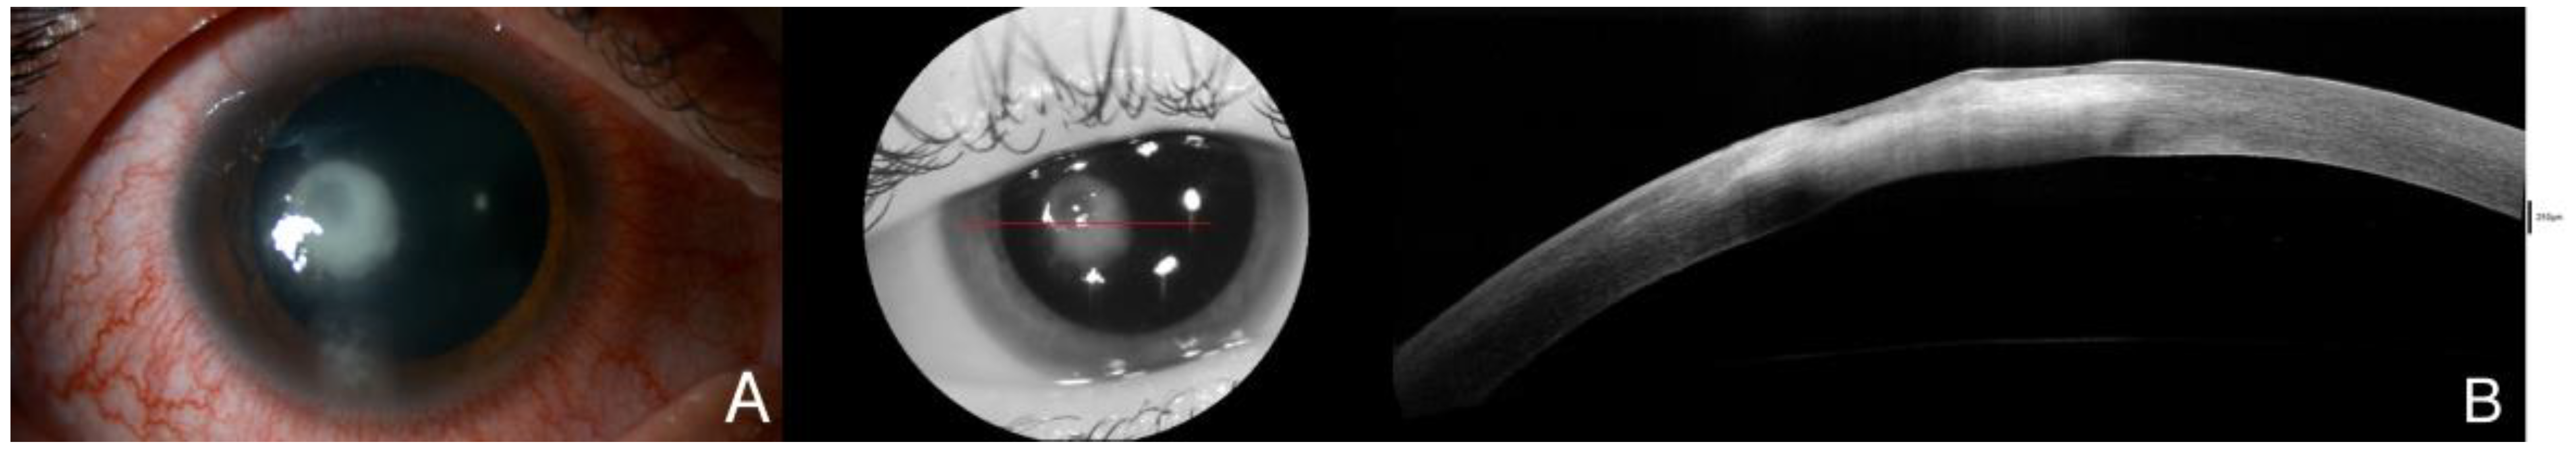

Figure 4.

Four days after surgery, the infiltrate kept becoming smaller, and as soon as the epithelial defect disappeared, corticosteroid therapy was initiated. After clinical improvement, slip lamp examination (A) demonstrated a reduced infiltrate with epithelial healing in AS-OCT (B), although hyperreflectivity remained due to the beginning of the leukomatous phase. Due to corneal scarring, stromal thinning could also be found in AS-OCT. The red line is correspondene of the en face picture with the selected section on the AS-OCT.